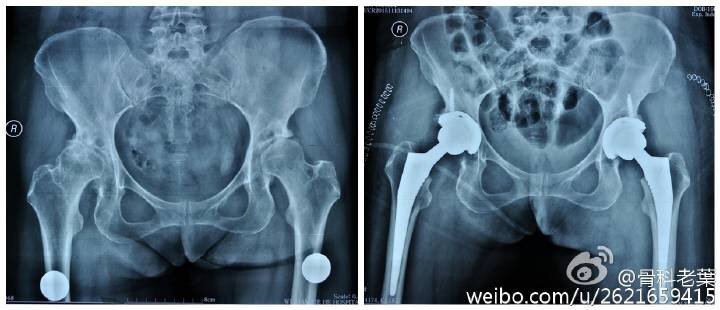

另附典型病例若干: